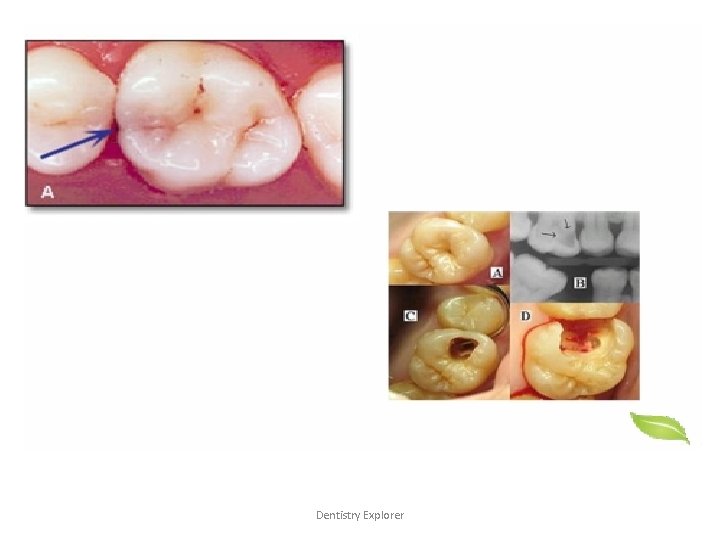

Indications for Operative Treatment Caries, Malformed, discolored, non-esthetic or Fractured teeth, Wearing of teeth (attrition, abrasion, etc. ) Restoration replacement or repair. Dentistry Explorer